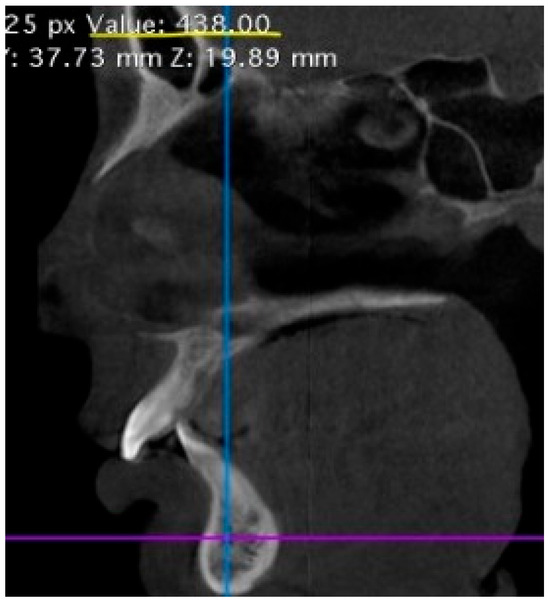

3.2. Radiological Bone Density of the Jaws, Hounsfield Index Analysis